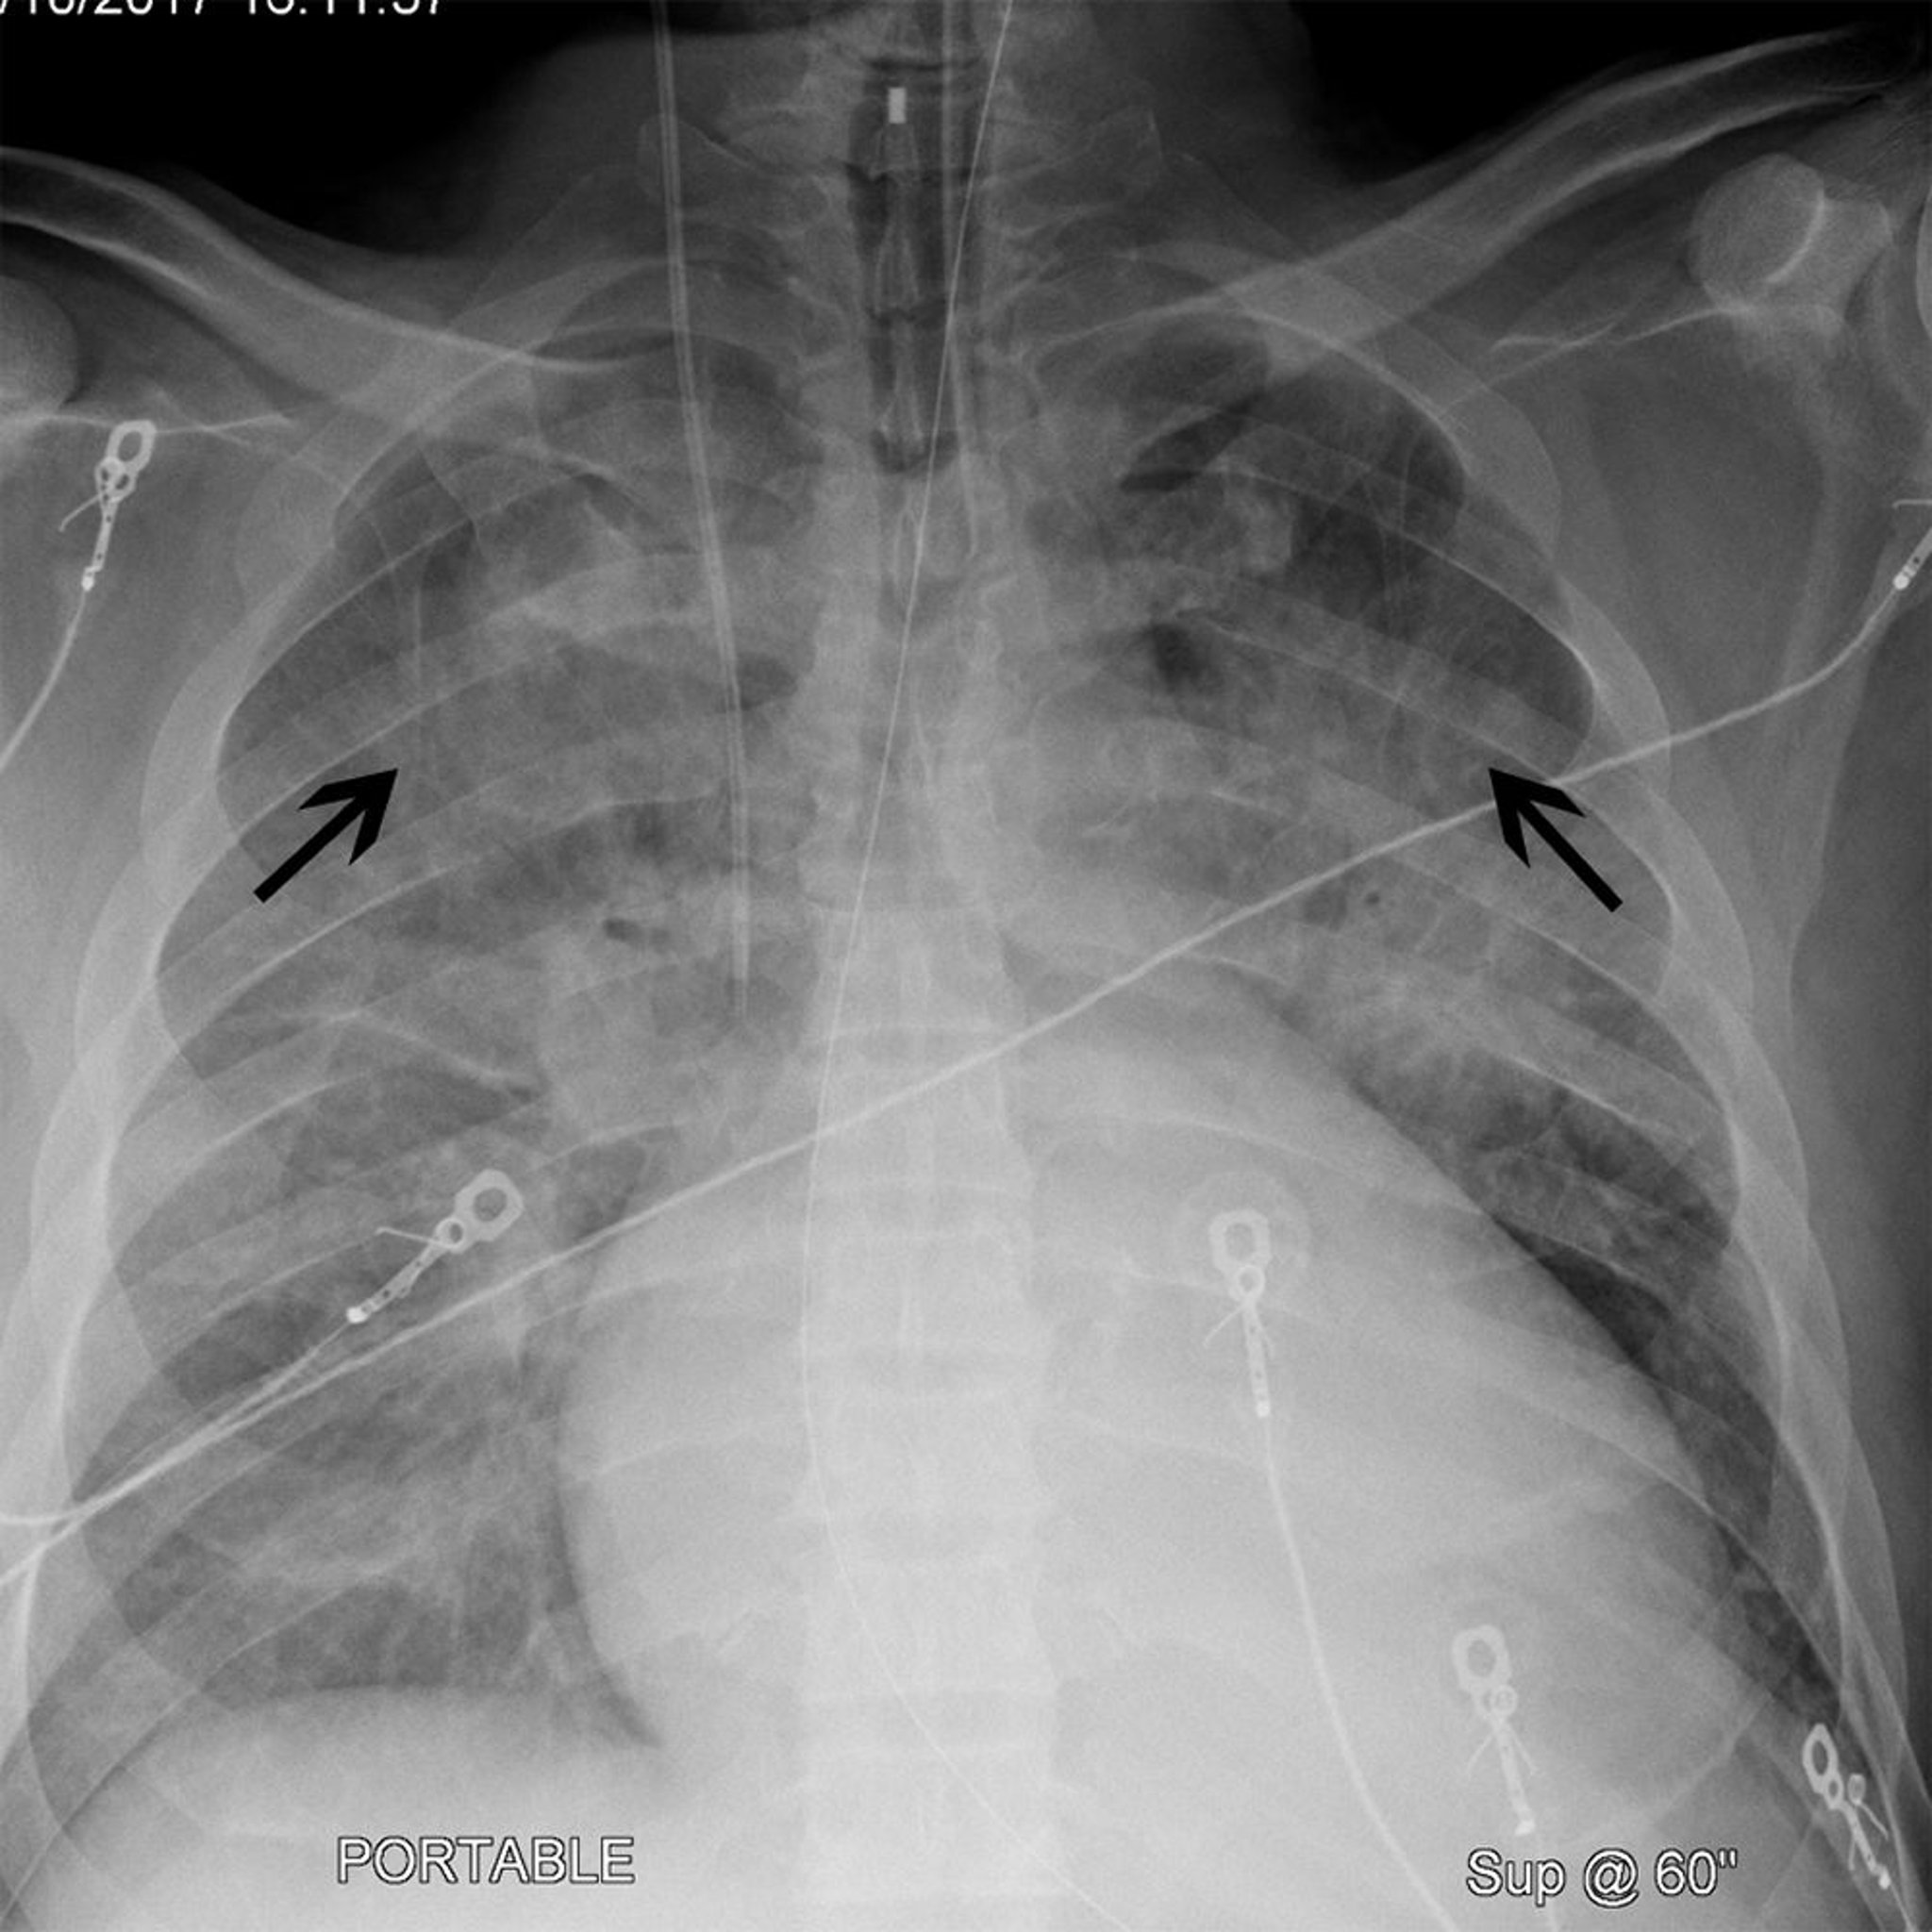

心拡大とcephalization(角出し像)を認める胸部X線写真

この患者には心拡大がみられる(胸部X線後前像で心陰影の幅が胸郭の50%を超えている)。Cephalization(角出し像)(黒矢印)もみられ,これにより上葉の肺血管がより顕著になっている。これらの所見は心不全患者でしばしば認められる。